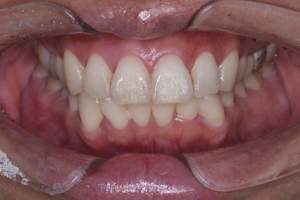

PMTC・オフィスホワイトニング

治療前

治療後

| 年齢 | 46歳・男性 |

| 主訴 | 着色を取りたい・歯を白くしたい |

| 治療内容 | PMTC・オフィスホワイトニング |

| 治療期間 | 90分 |

| 費用 | PMTC 5,500円 オフィスホワイトニング2回 6,600円(自費 診療) |

| リスク・副作用 | ・生活習慣(喫煙・コーヒーなど)により再度着色することがあります ・詰め物や被せ物はホワイトニングでは白くなりません ・ホワイトニングの効果は永久的なものではなく徐々に色戻りが起こります ・ホワイトニング後は歯の表面の水分量が一時的に少なくなりしみることがあります ・保険適用外の施術です |